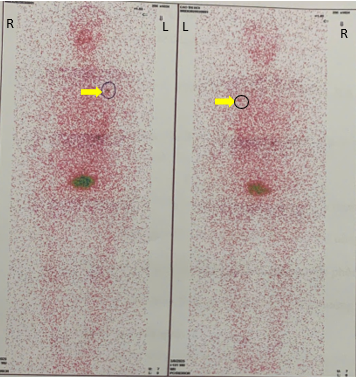

Sau uống I-131, người bệnh được theo dõi tại phòng cách ly, xạ hình toàn thân sau điều trị và ra viện khi đã đảm bảo an toàn bức xạ cho cộng đồng, tái khám sau 1 tháng để đánh giá và theo dõi kết quả điều trị.

Hình 5. Hình ảnh xạ hình toàn thân sau điều trị I-131: tăng hoạt độ phóng xạ tại vùng ngực trái (mũi tên vàng).